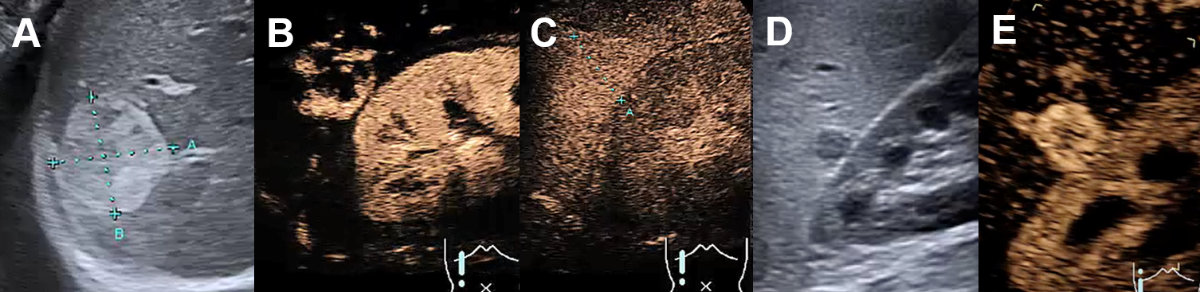

Conventional ultrasound is the first imaging modality to detect hepatic haemangioma. Most haemangiomas can be demonstrated as hyperechoic (78%) (figure 12A) but also as hypoechoic (15%) (figure 12D) or isoechoic lesion (7%) [42].

Figure 12Haemangioma on conventional ultrasound and CEUS. A Hyperechogenic haemangioma on ultrasound, B with centripetal contrast enhancement on CEUS in the arterial phase, C with complete contrast enhancement and without wash-out in the late venous phase. D Hypoechogenic hemangioma next to the kidney on ultrasound. E Complete contrast enhancement on CEUS in the arterial phase.

In the presence of risk factors (table 1) a contrast-enhanced imaging modality is mandatory to exclude malignant focal liver lesions (e.g., hyperechoic liver metastasis, figure 20A). CEUS is accurate for the diagnosis of haemangiomas in about 95% of the cases [3]. The peripheral nodular enhancement with gradual centripetal filling (= iris-diaphragm sign) without washout is a highly specific finding for a typical haemangioma [1, 42]. CEUS can classify these lesions as incomplete (22%) or complete (78%) centripetal filling haemangioma [3, 17]. Atypical features include “shunt haemangiomas” with abundant arterio- (porto-)venous shunts (also called high-flow or flash-filling haemangiomas) mostly with a hypoechoic appearance on conventional ultrasound (figure 13A), sclerosing haemangiomas and haemangiomas with regressive changes such as calcifications, thrombosis and phleboliths [42–44]. The findings of CEUS are characterised with similar but faster centripetal contrast-enhancement in high-flow haemangiomas (figure 13).

Figure 13Shunt haemangioma on conventional ultrasound and CEUS. A Hypoechoenic high flow shunt-hemangioma on ultrasound, B with rapid arterial centripetal filling in few seconds on CEUS with C arterioportal shunt (arrows) in the arterial phase.